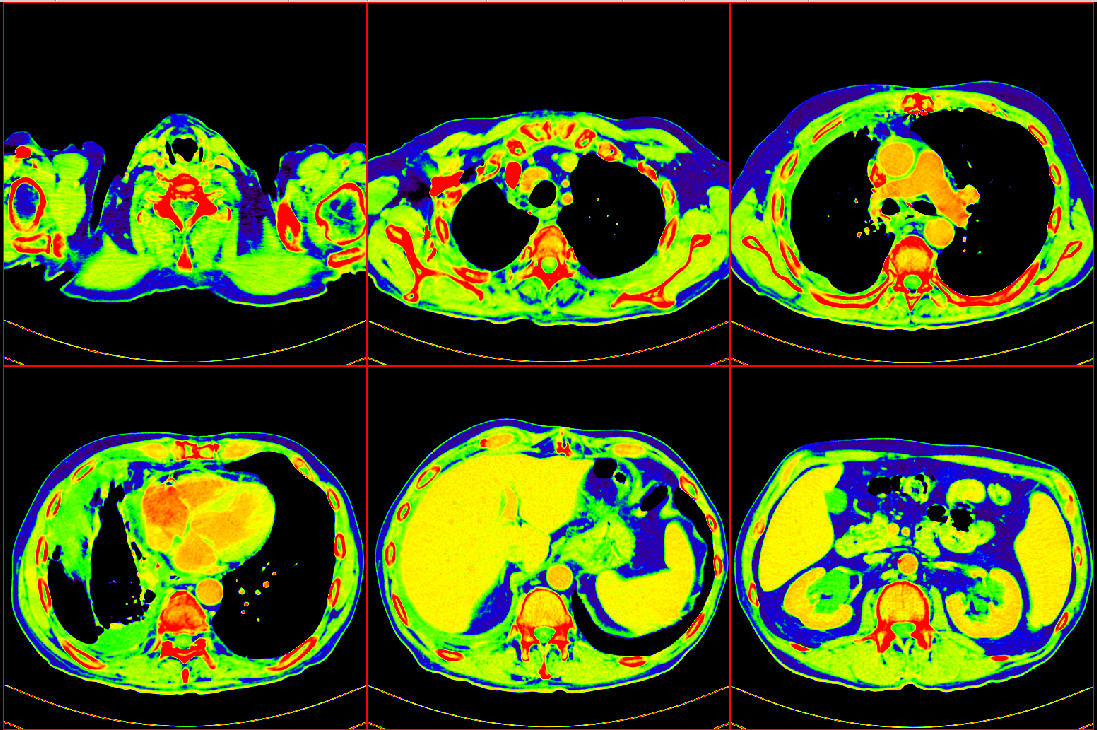

TCIA-TCGA-OV 癌症CT影像数据

TCIA-TCGA-OV 是一个癌症CT影像数据,源自癌症数据项目 The Cancer Genome Atlas (TCGA),旨在对各种类型的癌症诊治过程进行全程数字化的跟踪,以数字档案的形式记录检查结果、处方和疗效。